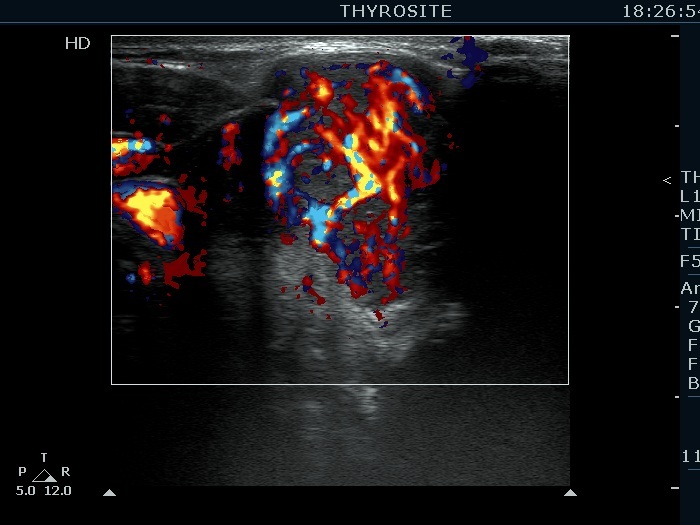

Right lobe, transverse scan, color Doppler mode. A chaotic-type vascular pattern is demonstrated.